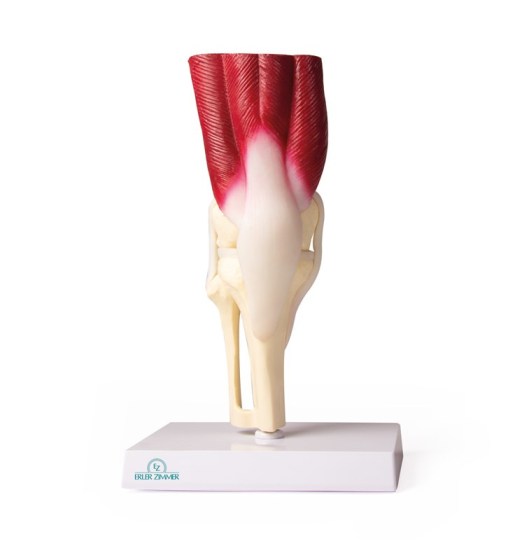

Kolenní kloub, životní velikost, se svaly

Katalogové číslo: EM270-4662

Dostupnost: Termín dodání ZDE

Cena s DPH3 351,70 CZK

Kolenní kloub ve skutečné velikosti se všemi důležitými svaly a vazy ( kolaterální vazy, meniskus, zkřížené vazy, patelární šlacha). Kloub není pohyblivý. Popisky německy / anglicky.

Na stojanu.

Rozměry: 8 x 24 cm

Hmotnost: 0,8 kg